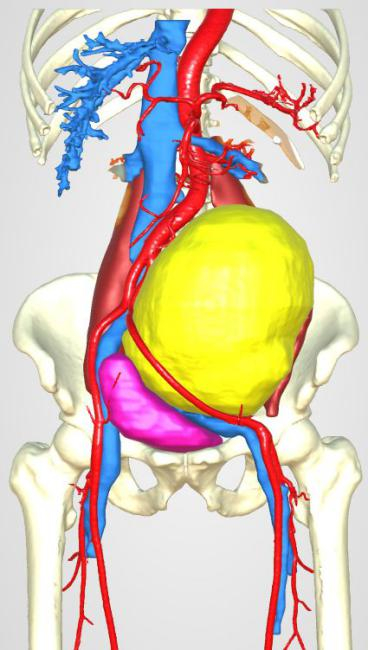

慧慧的小肚皮不过排球大小,而肚子里的肿瘤,几乎占据了腹部的大部分位置,把肠子都挤到了右侧腹部,把左肾挤到右下腹,把脾脏推向左上腹部。肿瘤周围遍布重要脏器及血管。

手术医生小心翼翼地分离肿瘤周围的组织,离断了供应肿瘤组织的血管,既要完整切除肿物,避免损伤瘤体包膜破裂,防止种植转移的发生,又要特别小心避开周围的重要脏器及血管。加上慧慧还是个小宝宝,脏器血管都极为稚嫩脆弱,医生们的动作缓慢轻柔,手术过程如同在嫩豆腐上绣花,难度非常大。

1个多小时后,慧慧肚子里的肿瘤被完整剥离、切除,离体后肿瘤重约1斤重。